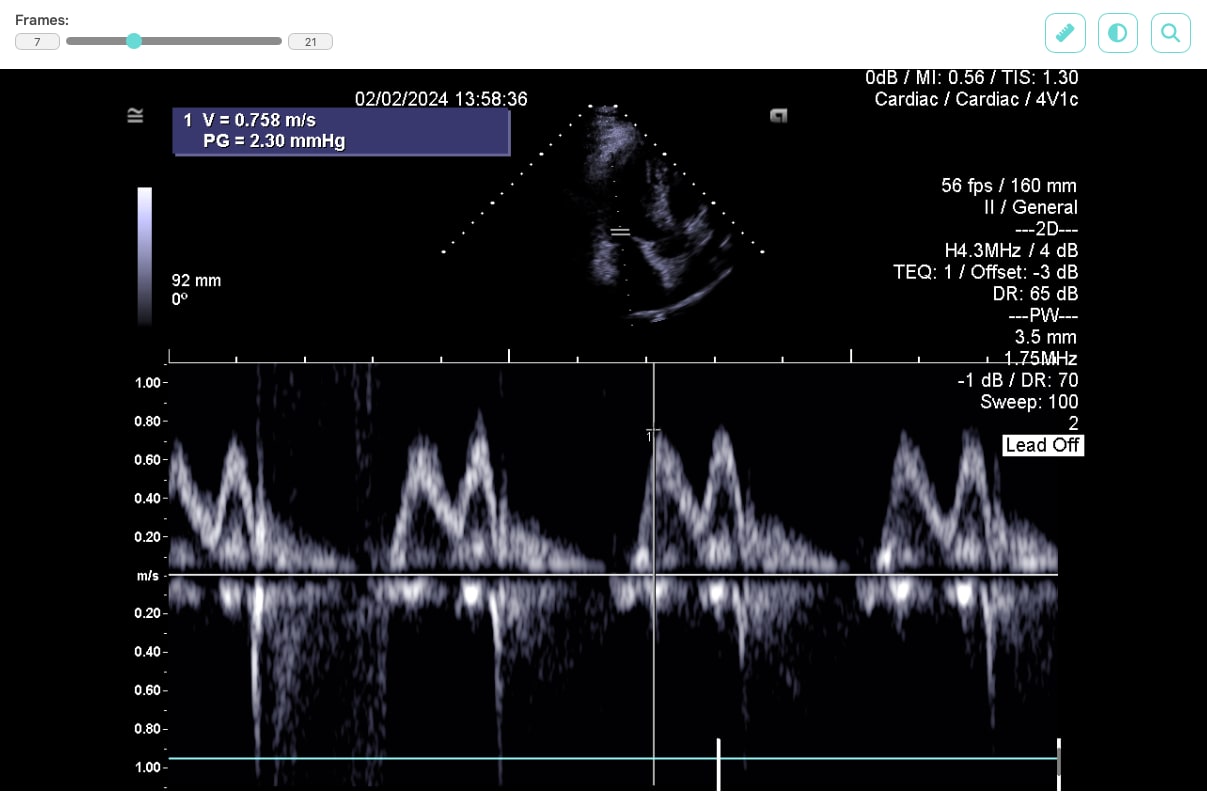

Our task was to design an optimal solution for displaying graphical results of patient examinations, captured using various imaging methods such as X-ray, CT, MRI, or ultrasound, directly within the clinic’s web application. It was necessary to consider both security requirements and the speed of processing large volumes of image data in the specialized DICOM format, which is the standard output format of medical imaging devices and the protocol through which medical devices communicate with each other.

For displaying data on the web, we selected the JavaScript library Cornerstone3D, which not only allows DICOM files to be viewed but also provides features such as adjusting brightness and contrast, or using a ruler to measure distances between displayed parts of the patient’s body.